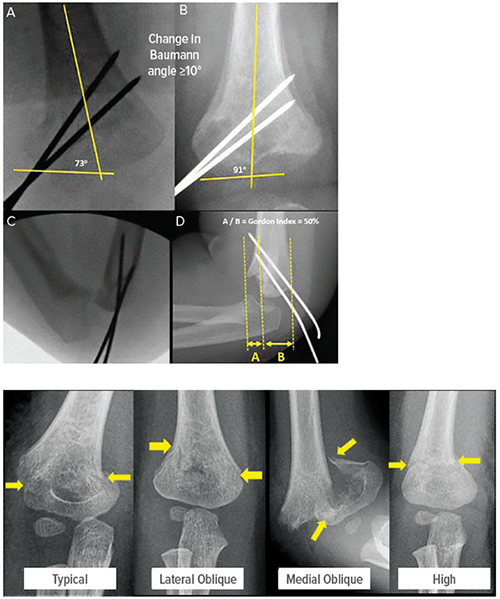

Supracondylar humeral fractures typically result from a fall onto an outstretched hand, which leads to a forced hyperextension of the elbow. When the researchers assembled the records of 103 patients who fit the study criteria, they were surprised to find that 69 cases involved females.

The study goes on to note that repairing these elbow fractures in such young children can be technically challenging. Of the 46 children diagnosed with bicolumnar fixation five (11%) demonstrated “loss of reduction,” or failure to fully close the fracture. However, among 55 patients with fixation of only the lateral column, 20 (36%) demonstrated loss of reduction.